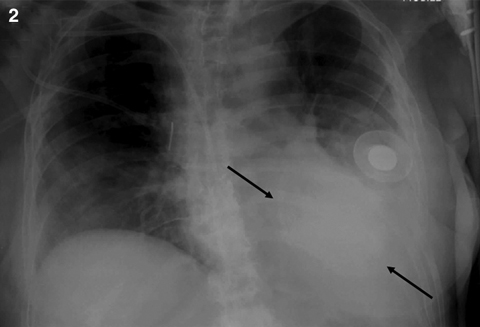

On the GHPS (Figure 1) a radiolucent pericardial halo was apparent, raising concerns for pericardial effusion. The rest of the study was unremarkable, with normal regional wall motion and quantitative ejection fraction of the cardiac ventricles. Comparison with a recent chest x-ray (Figure 2) revealed radiolucency external to the chest wall. Subsequent transthoracic echocardiography (Figure 3) ruled out the presence of pericardial effusion.

2: Anteriorposterior chest x-ray showing the saline-filled breast implant as a radio-opaque shadow on the left anterior chest wall (arrows). |